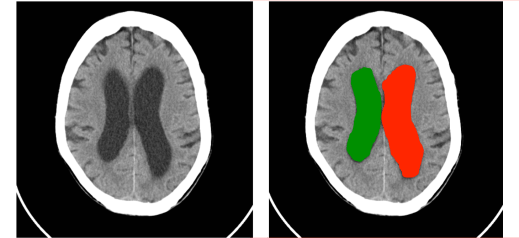

En un estudio retrospectivo de resonancia magnética de 2536 hombres jóvenes sanos de edades entre 17 y 35 años, media de 20,5 años, las variantes anatómicas normales estaban presentes en el 18,45%con la siguiente distribución: cavum vergae, 4,77%; grandes cisternas basales, 1.74%; quistes de la glándula pineal, 3.43%; espacios perivasculares ampliados, 2.56%; asimetría de los ventrículos laterales, 2.68%; lesiones de sustancia blanca aisladas, 2.6%; osificación de la hoz cerebral, 0.32%; y silla turca vacía, 0,35% (3).